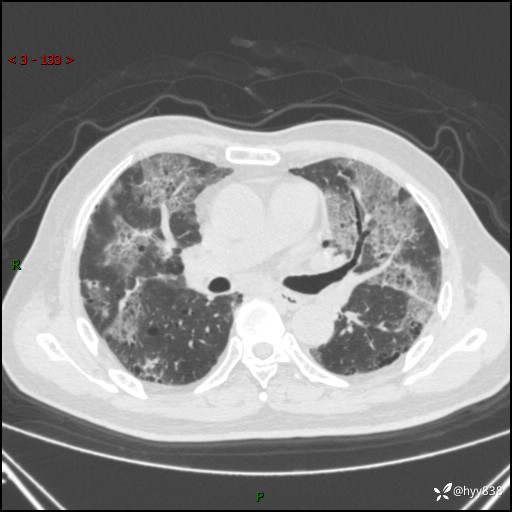

患者性别:男

患者年龄:64岁

简要病史:肝内胆管癌综合治疗后2周余,咳嗽、发热,咳白色泡沫痰。

临床诊断:感染?

讨论:病变性质?